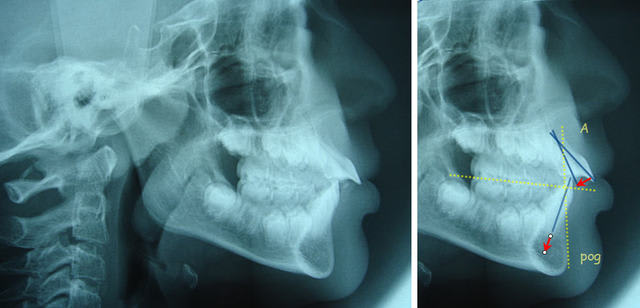

hyperdivergence

mon cher adhoc, on aurait plutot une pro-corono-vestibulie Sup.

Ancrage 6 et 7 par légére mesio version radiculaire . Puis un arc de retraction et des elastics et du torque et ca doit marcher sans peine. Bon, faut quand meme modéliser avec peut etre une analyse télé et un wax-up, ca serait mieux.

Pourquoi récidive assurée ? A cause de l’ascension de l’épine nasale antérieure ?

Dancha ,sur la tele de profil, tu notes une ingression des insicives du bas mais je vois pas trop comment tu fais sans appareiller tout le bas et un niti .10 thermique ( si je ne fais pas erreur)

Il n’y a pas beaucoup de mouvement à faire. En fixe, tu pourras réaliser une véritable ingression incisives, par contre en mobile ce sont surtout les autres dents qui égresseront.... Le fil .010 est un fil plutôt fait pour d’alignement, il est trop faible pour de l’ingression. Que tu la réalises en segmentaire avec un arc de base ou en arc continu, il te faudra un fil plus gros. Utilise donc ta technique habituelle.